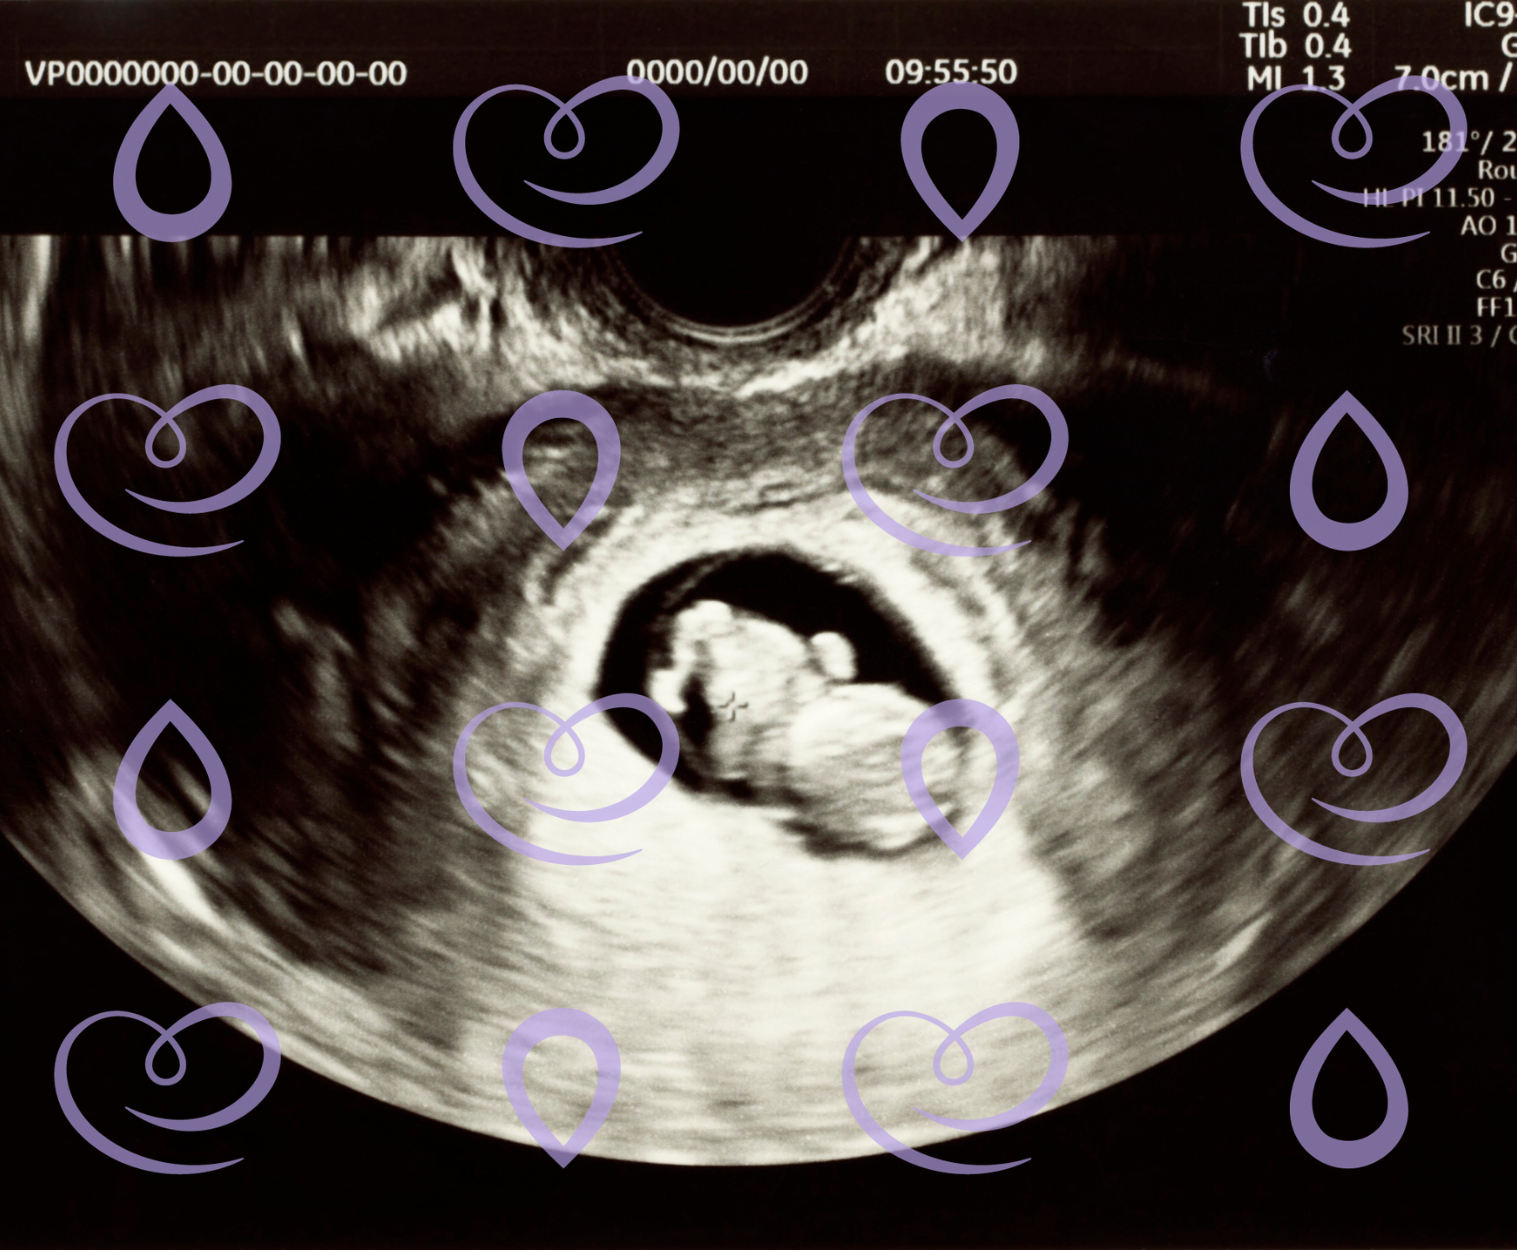

Durante a gestação, é comum que surjam dúvidas sobre os tipos[…]

O início da gestação costuma ser um período de muitas emoções,[…]